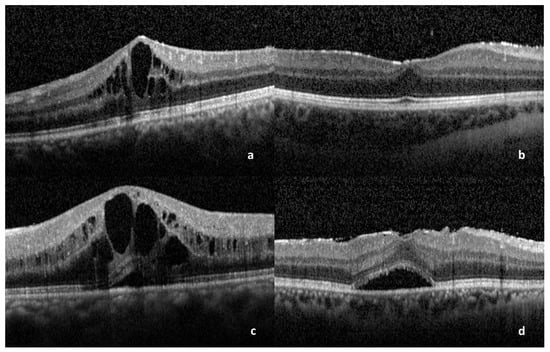

3. Results